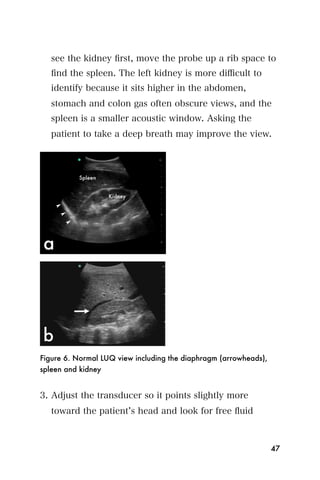

compression of the vena cava in the supine pregnant

patient. Ultrasound in the 2nd and 3rd trimester can be

used to determine the age of the pregnancy if last

116

menstrual period information is not known, evaluate the

placenta for previa, evaluate the cervix for premature

shortening or opening, assess causes for enlarged fundal

size, such as multiple gestation or excess amniotic fluid,

and finally to evaluate fetal heart rate. Further

ultrasound exams can be done to evaluate for fetal

anomalies and birth defects, but will not be discussed in

this chapter.